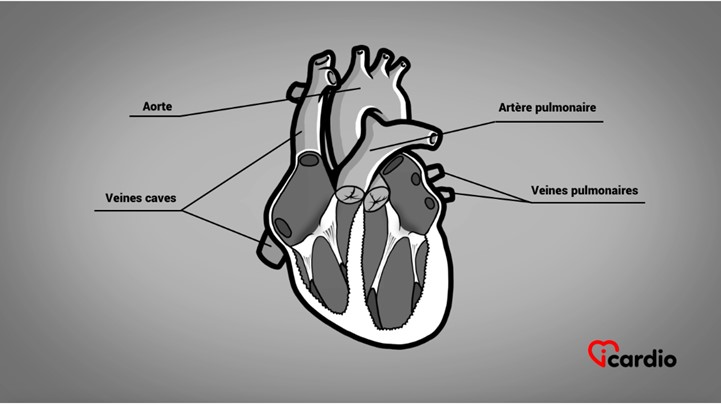

Le cœur est formé de 4 parties appelées cavités. Les 2 cavités supérieures, les oreillettesLes oreillettes sont les deux cavités supérieures du cœur. Elles agissent comme des réservoirs du sang qui ira remplir les ventricules. >>, sont les réservoirs du sangLe sang est composé de globules rouges, de globules blancs, de plaquettes et de plasma. Les globules rouges sont responsables du transport de l’oxygène et du dioxyde de carbone. Les globules blancs constituent notre système de défense >> qui ira remplir les ventriculesLes ventricules sont les 2 cavités inférieures du cœur. Ils sont plus musclés que les oreillettes; ils servent à propulser le sang pour assurer la circulation dans tout le corps. >>.

Les ventriculesLes ventricules sont les 2 cavités inférieures du cœur. Ils sont plus musclés que les oreillettes; ils servent à propulser le sang pour assurer la circulation dans tout le corps. >> sont les 2 cavités inférieures du cœur. Ils sont plus musclés que les oreillettesLes oreillettes sont les deux cavités supérieures du cœur. Elles agissent comme des réservoirs du sang qui ira remplir les ventricules. >>; ils servent à propulser le sangLe sang est composé de globules rouges, de globules blancs, de plaquettes et de plasma. Les globules rouges sont responsables du transport de l’oxygène et du dioxyde de carbone. Les globules blancs constituent notre système de défense >> pour assurer la circulation dans tout le corps.

Les oreillettesLes oreillettes sont les deux cavités supérieures du cœur. Elles agissent comme des réservoirs du sang qui ira remplir les ventricules. >> et les ventriculesLes ventricules sont les 2 cavités inférieures du cœur. Ils sont plus musclés que les oreillettes; ils servent à propulser le sang pour assurer la circulation dans tout le corps. >> s’assemblent sur 2 gros anneaux qu’on appelle les anneaux auriculo-ventriculaires.

Les 2 autres anneaux sont plus petits. Ils rattachent l’artère pulmonaire au ventricule droit et l’aorte au ventricule gauche.

2 de ces valves cardiaques sont la valve pulmonaire et la valve aortiqueLa valvule aortique est située entre le ventricule gauche et l’aorte. C’est l’une des quatre valves du cœur. >>. Elles sont situées à la base des gros vaisseaux, soit à la sortie des ventriculesLes ventricules sont les 2 cavités inférieures du cœur. Ils sont plus musclés que les oreillettes; ils servent à propulser le sang pour assurer la circulation dans tout le corps. >>.

Les 2 autres valves cardiaques sont les valves auriculo-ventriculaires qui séparent les ventriculesLes ventricules sont les 2 cavités inférieures du cœur. Ils sont plus musclés que les oreillettes; ils servent à propulser le sang pour assurer la circulation dans tout le corps. >> des oreillettesLes oreillettes sont les deux cavités supérieures du cœur. Elles agissent comme des réservoirs du sang qui ira remplir les ventricules. >>.